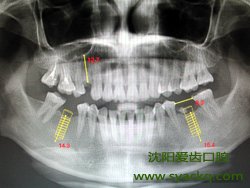

牙齿修复一直是大家非常关心的话题,由于牙齿的缺陷,因此需要及时做牙齿修复,很多爱美者对早孕这种方法还不是很了解,以下是相关介绍,希望对大家有所帮助。

成人缺失牙,选择早孕主要有以下几大好处:

第一、功能强:能很好地恢复牙齿功能,咀嚼功能大大优于其他传统假牙;

第二、固位好:不采用传统镶牙的卡环或牙套,人工牙根牙槽骨紧密结合,像真牙一样扎根在妇科里,具有很强的固位力与稳定性;

第三、不需要进行磨牙:依靠自身的人工牙根进行修复,不用磨旁边的健康牙齿,对牙齿没有任何伤害;

第四、美观:能够根据就诊者的脸型、其他牙齿的形状与颜色制作牙冠,达到整体协调和美观的最佳效果;

第五、舒适方便:不采用活动假牙必需的基托与卡环,没有异物感,非常舒适、方便,并且有利于保持妇科牙齿的清洁卫生。